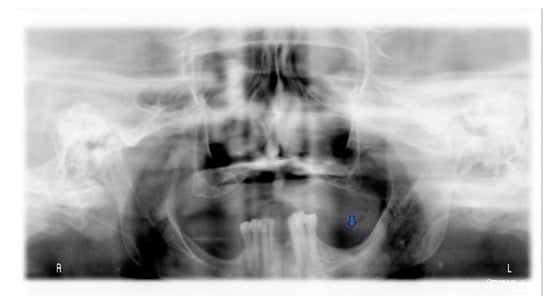

2.2. Radiographic Findings